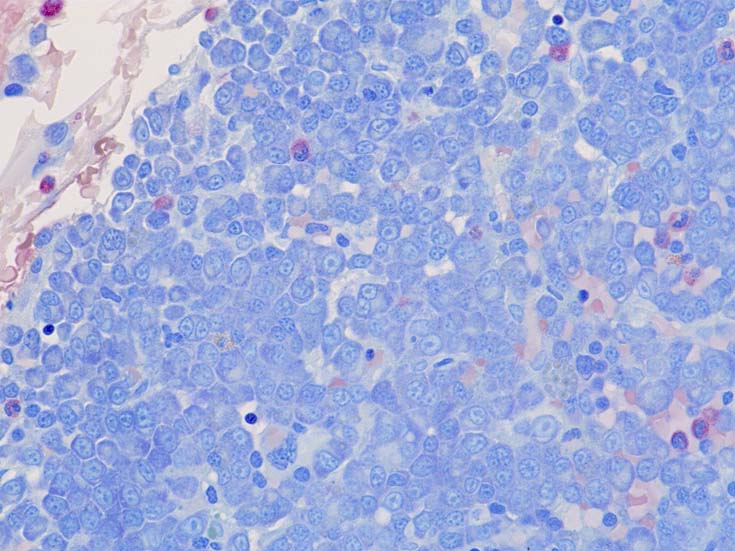

normal plasma cell, myeloma cell, plasmacytoma(bone)の細胞組織像

(サムネイル画像のクリックで大きな画像が見られます) 1-3はASD-Giemsa染色. 4はHE.